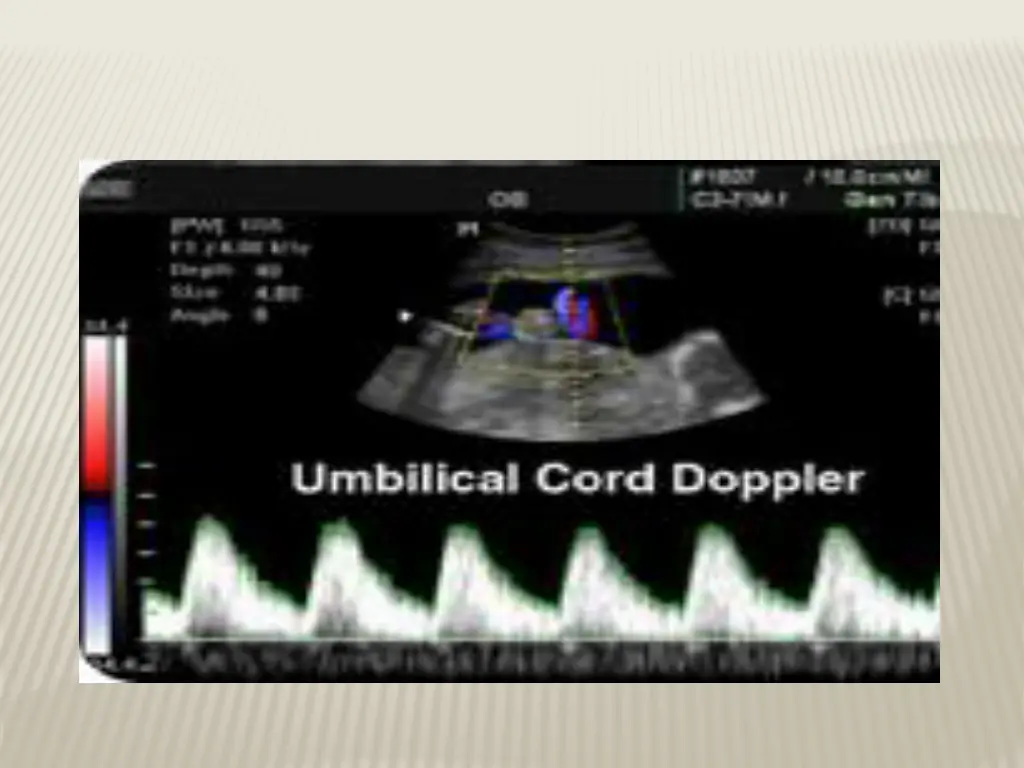

DOPPLER VELOCIMETRY Measurement of blood flow velocities in maternal & fetal vessels Reflect feto-placental circulation Doppler indices from UA, Uterine A & MCA Doppler studies is mostly valuable IUGR In IUGR absent or reversed EDF (end diastolic flow) associated with fetal hypoxia